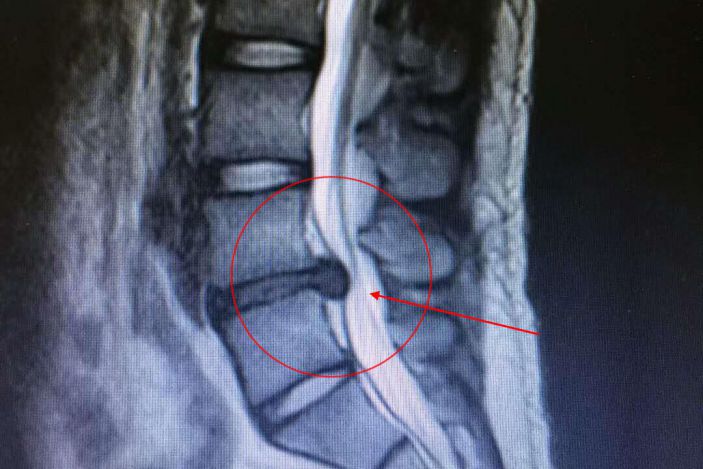

爲得到科學診治,賴某慕名于3月26日來康美醫院住院。經MRI檢查發現,患者椎間盤變性,L4/5椎間盤右後突出,右側神經根受壓。

3月28日,我院外四科吳志斌主任帶領團隊爲其實施經側路鏡L4/5椎間盤髓核摘除術。通過摘除突出髓核,解除對神經根的壓迫,達到根治目的。術後患者疼痛消失,直腿擡高試驗85度(-),手術非常成功。

據吳主任介紹,賴某的椎間盤突出并且部分疝入椎管内,壓迫神經根,神經根充血水腫,這種情況通過牽引等傳統治療難以根治,甚至還會加重病情,隻能通過手術治療。患者年紀較輕,傳統手術創傷大、出血多,術後往往加劇脊柱退變。而采用脊柱微創手術,傷口很小,隻有0.75厘米左右,術後恢複快。通過摘除突出的髓核,解除對神經根的壓迫,使神經根完全松解,手術後患者疼痛症狀即可消失,3天左右即能康複出院。